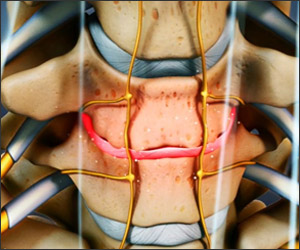

DEGENERATIVE SPINE SURGERY

What Is Degenerative Spine Disease?

Spinal degeneration is a progressive disease, meaning it gets worse over time. Here’s how the disease progresses:

1. Over time, the fluid in the cushioning disc between the vertebra decreases, affecting the ability of the disc to function normally.

2. Fissures (small tears) can develop in the annulus, the outer layer of the disc, making it more susceptible to tears.

3. Vertebral endplates may thin, affecting the blood supply to the disc.

4. All of this causes the joints on the side of the vertebra to experience an increased workload, contributing to the degeneration.

The Effects of Spinal Degeneration

As degeneration occurs, minor trauma or unusual activity can produce back pain, causing muscle pain and spasms. The outer ring of the disc can tear and the inner cushioned part of the disc may continue to degenerate. Eventually, this can lead to spinal instability and nerve entrapment, which causes nerve pain.

• Bone spurs or osteophytes (bony growths) develop in and around the facet joint and discs.

• The ligaments can thicken and compress the spinal cord, causing central spinal stenosis or nerve root entrapment.